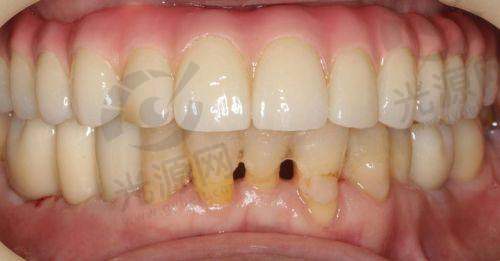

实例1:患者李女士在唐山协和口腔医院做了种植牙,选用的是韩国登腾种植体,手术十分顺利,术后也没有明显的肿胀,李女士表示非常满意,咀嚼能力明显提升。